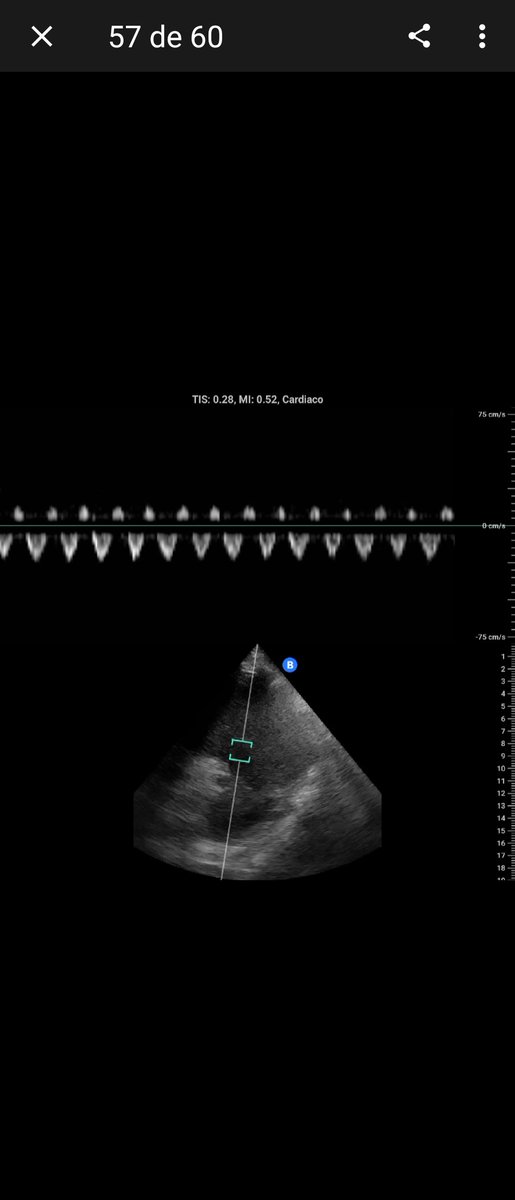

POCUS of the day: use M-mode to assess or rule out significant aortic stenosis. An opening >15 mm can rule it out, while <7 mm suggests severe AS. M-mode remains one of the most underrated tools for holistic bedside ultrasound assessment. #POCUS #POCUSFirst #FOAMED

intensivaev's tweet image. POCUS of the day: use M-mode to assess or rule out significant aortic stenosis. An opening &amp;gt;15 mm can rule it out, while &amp;lt;7 mm suggests severe AS. M-mode remains one of the most underrated tools for holistic bedside ultrasound assessment. #POCUS #POCUSFirst #FOAMED